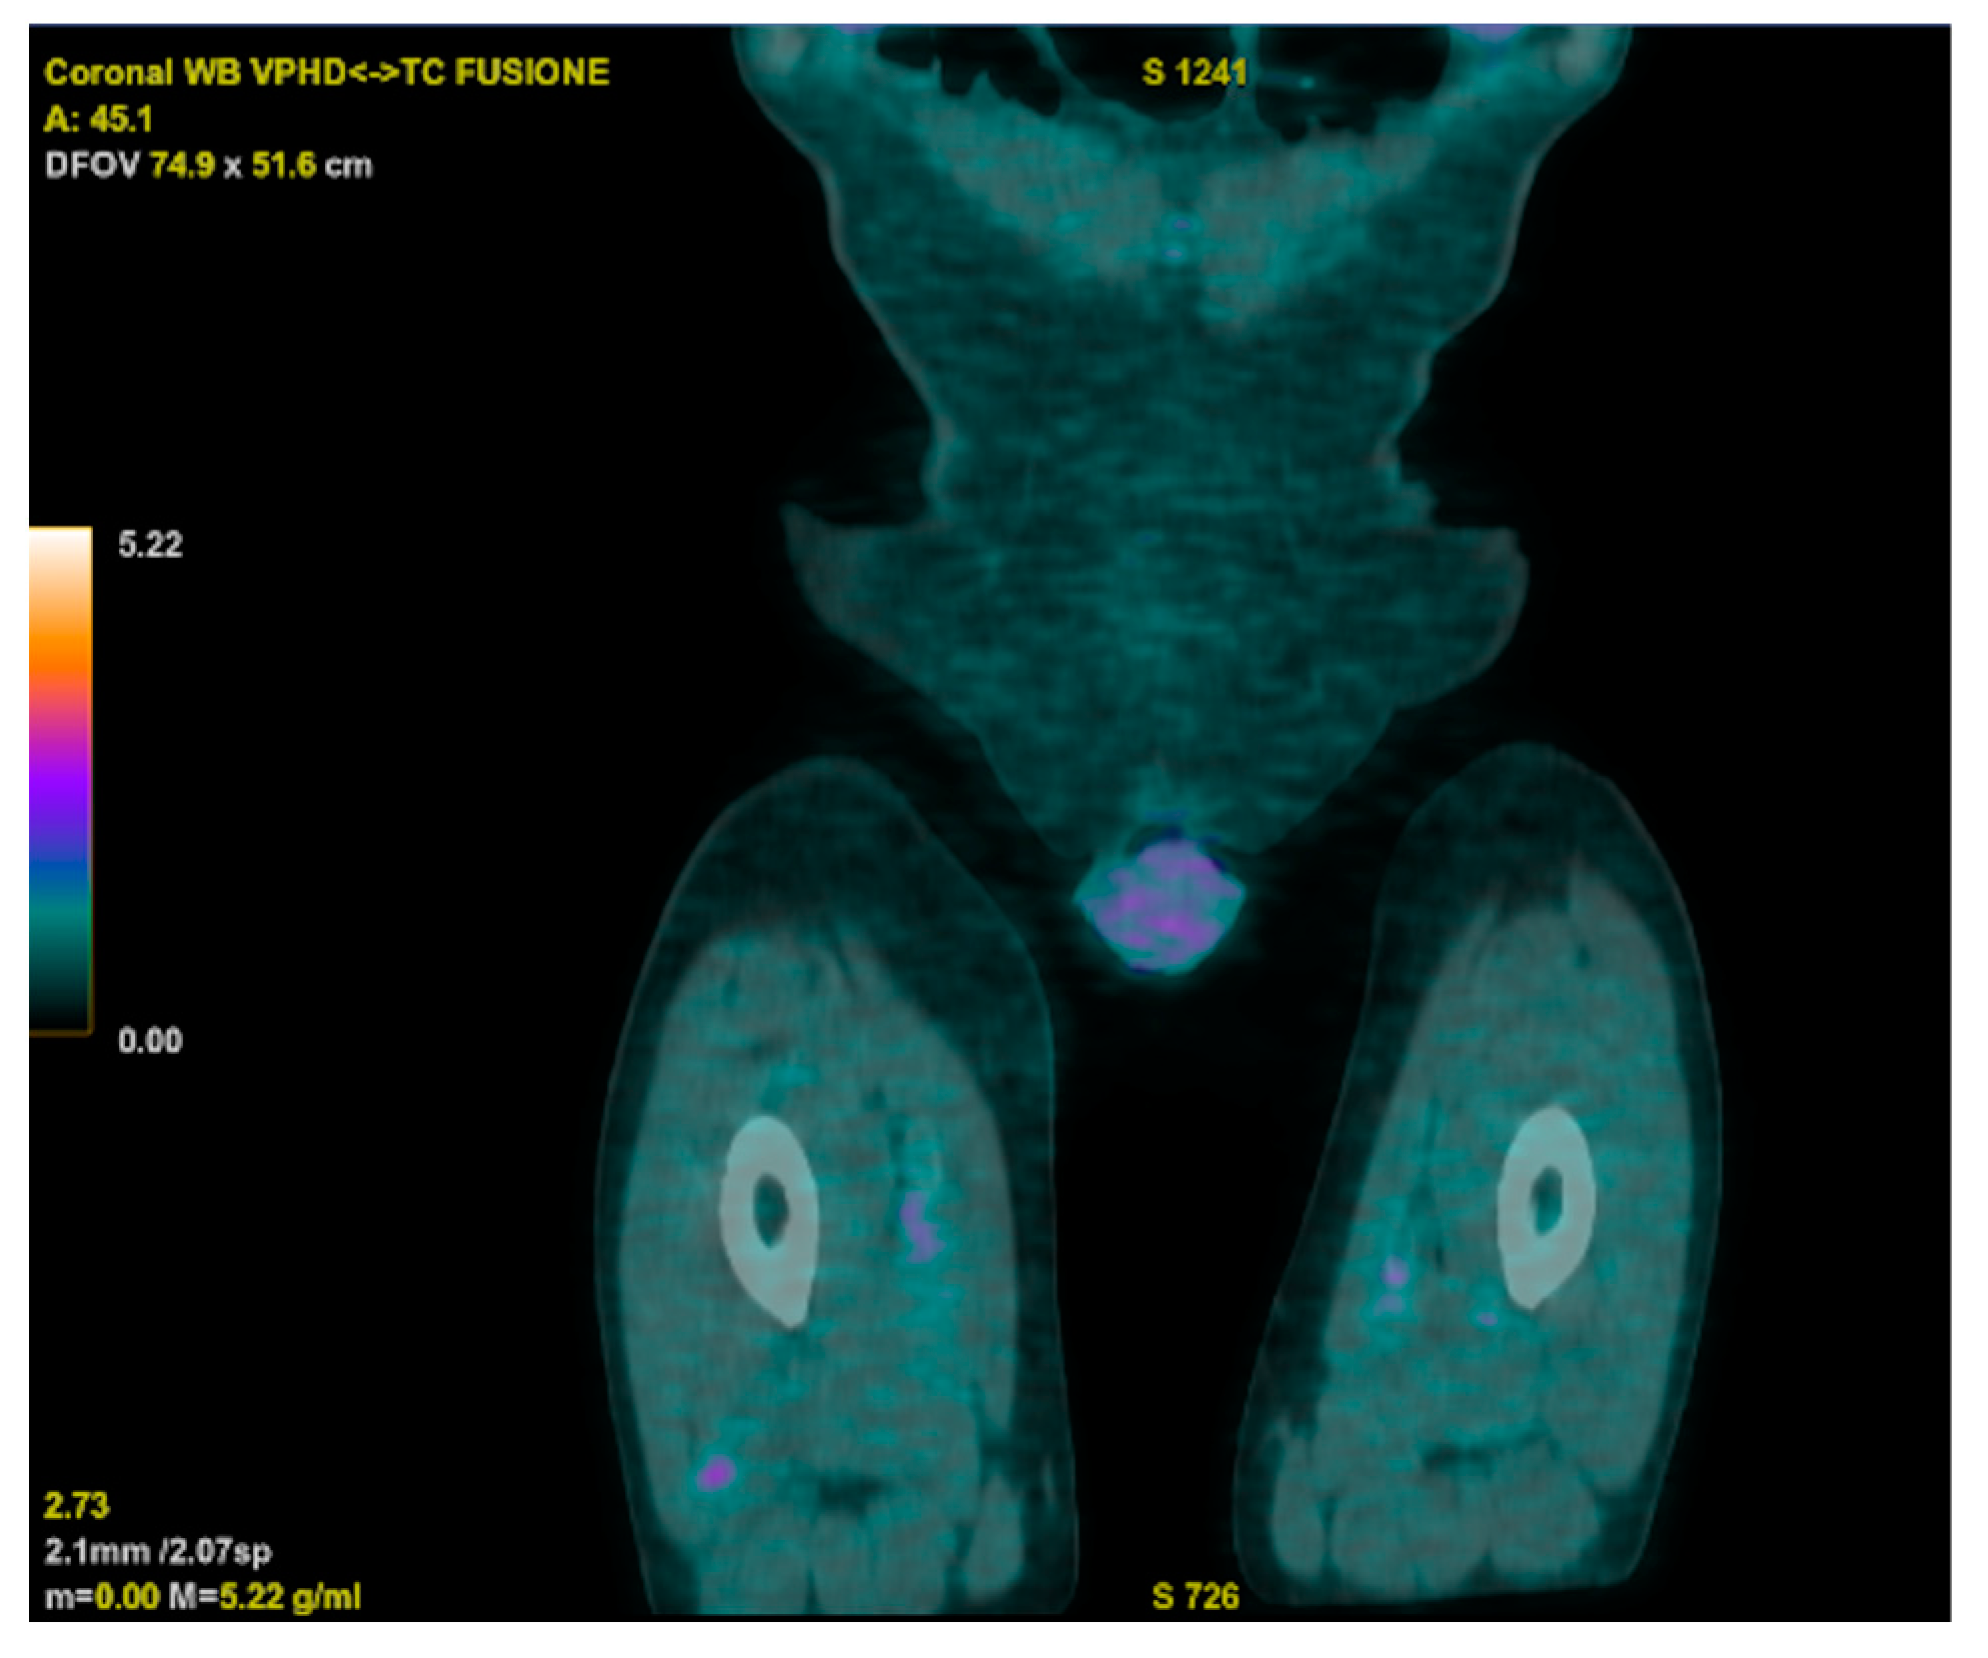

Meanwhile, an 18 FDG PET-CT displayed increased metabolic activity close to the prosthetic aortic valve, and a trans-esophageal echocardiogram raised suspicion of endocarditic vegetation. However, a subsequent cardiac CT ruled out vegetations but unveiled the persistence of a residual VSD. The cardiac surgeon indicated that a surgical approach was not necessary, considering the adequate functioning of the prosthetic valve. The PET-CT also revealed two hypercaptant lesions in the patient’s right thigh that were further investigated, with a biopsy showing a histiocytic inflammatory infiltrate and a specimen that was deemed suitable for microbiologic cultures (Figure 3).

Figure 3.

18 FDG PET-CT showing two hypercaptant lesions in the patient’s right thigh.